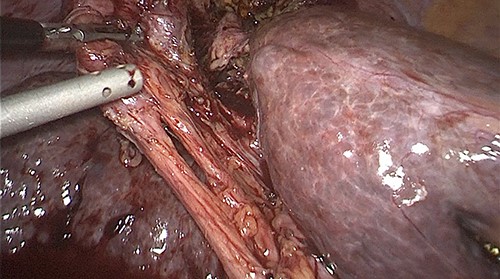

Prior to the surgical protocol, prophylactic antibiotics (ceftriaxone 1 g and metronidazole 500 mg) were administered during anesthetic induction. Three trocars were placed to perform the surgical procedure, one 11 mm supraumbilical (optical) and two 5 mm in the epigastrium and in the right upper quadrant. Pneumoperitoneum was induced with closed technique and the patient was placed in the reverse Trendelenburg position to begin the procedure. Inside the abdominal cavity, we observed the gallbladder adhered to the diaphragm (Fig. 2). The gallbladder was dissected, leaving the fundus of the gallbladder attached to the diaphragm (Fig. 3), the pleura and its movements were not appreciated, and lung tissue was not identified through the orifice. We could see a thick inflammatory tissue sealing the defect. Two giant stones were removed from the gallbladder’s fundus (Fig. 4) and the gallbladder was dissected antegrade. Cystic artery and duct were identified using Strasberg’s critical view of safety (Fig. 5). One distal and two proximal staples were placed in the cystic duct and cut, as well as a distal and one proximal staple in the cystic artery to cut as well. Later the gallbladder and stones were removed. Before ending the procedure, a drain was placed into the surgical wound, hemostasis was checked, and trocars were removed under direct vision. Finally, the fascia was closed with a 1–0 absorbable suture and the skin is closed with a 4–0 suture. There was no complications nor side effects in the mediate and immediate postoperatory.

Cystic artery and cystic duct identified by using Strasberg’s critical view of safety.